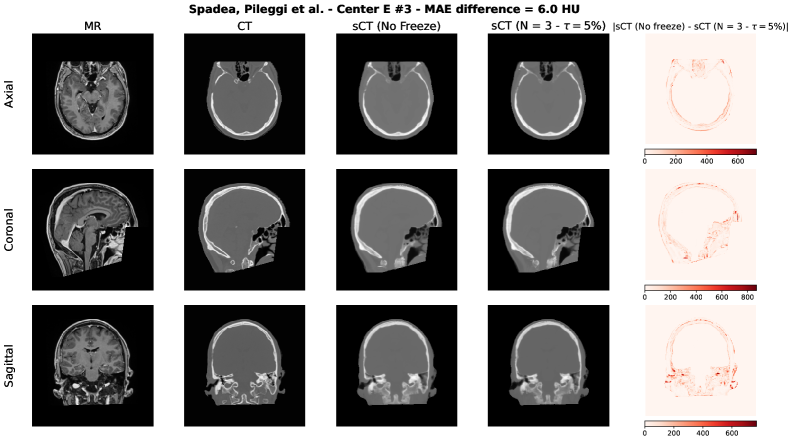

To qualitatively assess the potential impact of the adaptive freezing strategy on the generated synthetic CTs (sCTs), we conducted a visual comparison between the sCTs obtained with and without the proposed methodology. For each model employed in the study, we selected two representative test cases based on the following criteria:

• The case with the minimum difference in terms of MAE, thus the lowest difference between the sCTs MAE generated with and without adaptive freezing.

• The case with the maximum difference in terms of MAE, thus the highest difference between the sCTs MAE generated with and without adaptive freezing.

Each figure presents the following for the axial, coronal and sagittal plane of the central slice:

1. 1.

Input MR image;

2. 2.

Ground-truth CT image;

3. 3.

sCT generated without adaptive freezing;

4. 4.

sCT generated with the proposed adaptive freezing, using 𝒩=3\mathcal{N}=3 and τ=5%\tau=5\%;

5. 5.

Absolute difference map between the two sCTs.

Figure S5: Spadea, Pileggi et al. architecture [37] – Minimum MAE difference case.

Refer to caption

Across all models and both selected cases, no relevant and systematic structural differences were observed. The differences highlighted in the absolute difference maps and the variation in MAE are attributable to the stochastic nature of the training process (e.g., batch shuffling and optimization path variability) rather than the direct effect of the adaptive freezing mechanism.

This findings are aligned with the results observed in terms of MAE, PSNR and SSIM presented in this study.